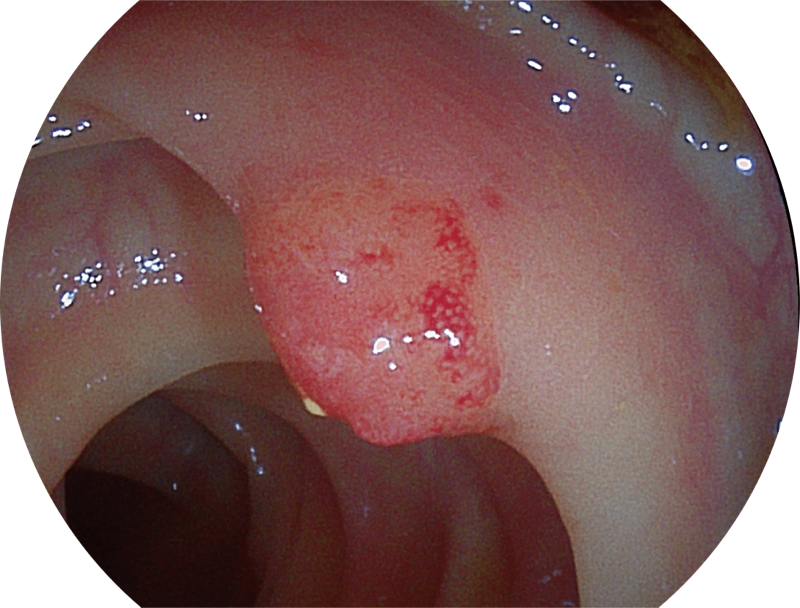

能够凸显黏膜浅层血管轮廓和黏膜表面微结构,适用于中、近景观察下的早癌精确诊断。